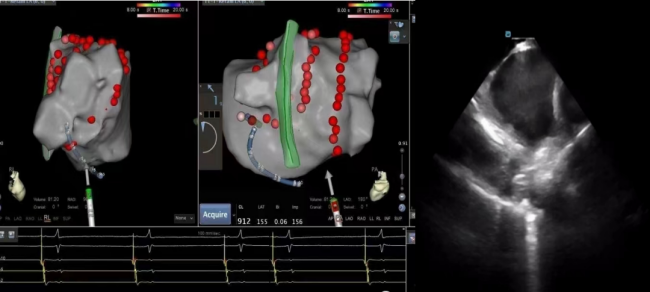

近日,立博体育 心血管内科团队为一“阵发性房颤、阵发性房扑”患者成功开展心腔内超声心动图(ICE)辅助下导管射频消融新技术,此项新技术的开展,标志着立博体育 心血管内科团队在心律失常的诊疗技术方面又迈上一个新的台阶。

68岁的张先生,因“阵发性房颤、阵发性房扑”就诊于心血管内科,完善相关检查提示心房颤动、心房扑动伴不固定型房室传导阻滞,非特异性ST段异常,具射频消融治疗指征,心血管内科团队经过缜密的术前讨论、方案制定,与患者及家属充分知情沟通后,成功实施ICE辅助下室早导管射频消融术。术后患者恢复窦性心率,未诉特殊不适。立博体育

心血管内科主任、主任医师蒋路平介绍,心腔内超声心动图(ICE)就像是心内科介入医生的“透视眼”,它是指在导管的顶端安置超清超声探头,经外周血管输送至心腔内部,对心脏及其邻近组织进行实时高质量成像和血流动力学测定的超声成像技术,犹如在心脏里长了一双明亮的眼睛一样,可以直观地观察心腔内结构,更清晰、精确定位完成手术,是各种心脏介入手术中重要的辅助工具。该项技术能更直观地显示心腔内结构及实时导管位置,有助于术者更精准快速地进行标测,显著提高了消融的成功率及安全性,减少了手术并发症,缩短了手术时间。心腔内超声心动图(ICE)还能有效运用在“左心耳”封堵术,避免患者术前全麻下食道超声的痛苦,及并发症发生,减少手术费用。

心腔内超声心动图,又名心腔内超声,医生更多用其英文缩写称呼其ICE。是近几年来国际心内介入领域兴起的一项新技术。运用心脏腔内超声就像在心脏里长了一双明亮的眼睛一样,可以直观地观察心腔内结构。

一些需要精准定位的特殊心律失常(如乳头肌室性早搏、希氏束旁室性早搏),通过ICE可以更快更便捷的进行解剖标测。三维心腔内超声能精准定位目标靶点,消融有的放矢,避免累及其他重要结构。